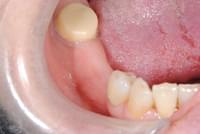

写真は、抜歯後の口腔内の写真です。見るからに、骨が少なく、陥凹してしまっていました。

写真は、実際の手術の写真で、丸く採取された骨片が、スクリューで固定されています。

骨の移植手術後、移植した骨片が生着するのを数か月待って、インプラント埋入手術を行いました。写真はその時のもので、移植した骨が周囲の骨と一体化して、しっかりと骨が増えているのが分かります。